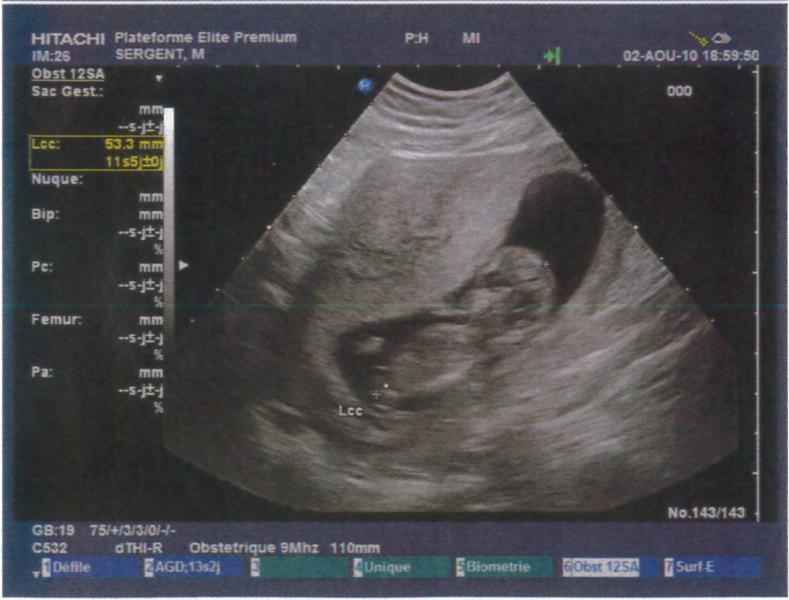

Je suis à 12SA soit 10SG, j'ai fait mon écho hier soir et tout va super bien !!! Je suis trop heureuse je vais vraiment pouvoir vivre ma grossesse à fond !! La nuque est parfaite, à vérifier par le test de la trisomie la semaine pro en même temps que la déclaration !!

Je vous met les photos des échos mais je trouve que l'on ne voit rien par rapport aux superbes images que nous avons vues !! Mais c'est pas grave, on a un super souvenir quand même !!

Pièces jointes

• echo1.jpg

echo1.jpg

53.6 KB · Affichages: 70

• echo2.jpg

echo2.jpg

53.8 KB · Affichages: 68

• echo3.jpg

echo3.jpg

52.7 KB · Affichages: 69

• echo4.jpg

echo4.jpg

55.4 KB · Affichages: 70

• echo5.jpg

echo5.jpg

50.7 KB · Affichages: 71